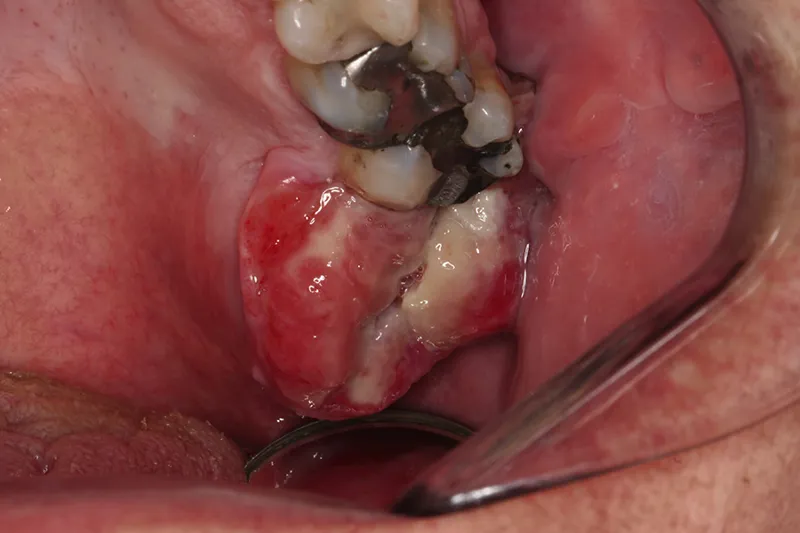

PATIENTTILFÆLDE – Et patientforløb på 3,5 måneder beskrives fra første kontakt hos praktiserende tandlæge til diagnosen, osteosarkom af maksillen, foreligger. Forløbet er langstrakt, dels fordi de tidlige tegn på oral cancer ikke genkendes, og dels fordi biopsien fra egen tandlæge var inkonklusiv.